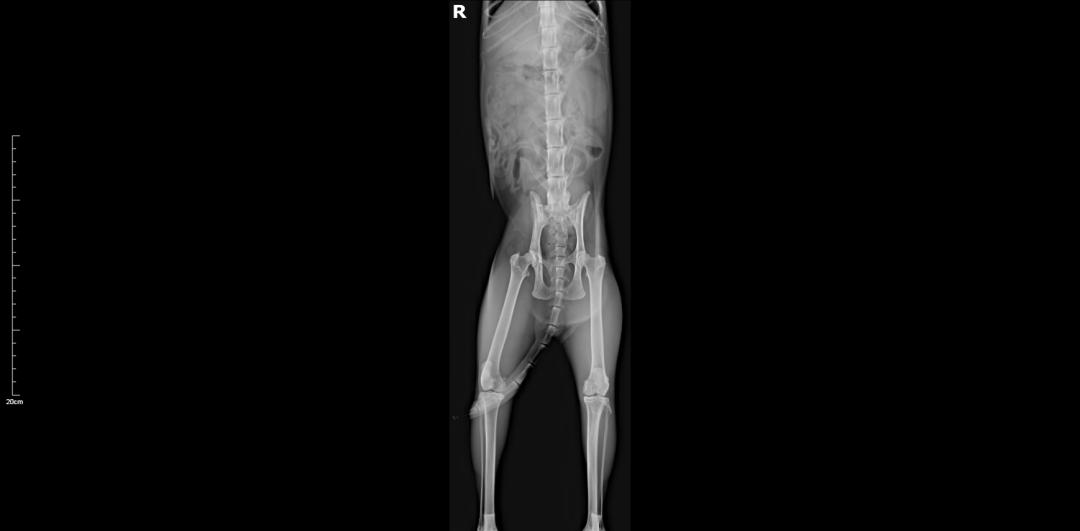

DR↓↓

胸腰椎、四肢未见明显骨折;面部、鼻腔、多处骨折。